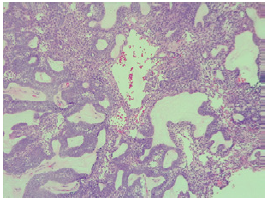

A contrasted CT scan of the neck and paranasal sinuses was performed, identifying a mass involving the left mandibular region and the pterigopalatine fossa with associated bone destruction; a biopsy with histopathological study report was also performed, showing follicular and plexiform ameloblastoma. Taking into account the findings of the tomography and the reports from the pathologist, ameloblastoma was diagnosed without a doubt. Extension studies were also performed with chest CT and cervical lymph node puncture biopsy, ruling out distant disease. The case was discussed during a multidisciplinary meeting where a left partial mandibulectomy, mandibular condyle reconstruction with plaque and fibula free flap were established as management. The pathology of the surgical specimen showed tumor-free edges and surgical margins of 10mm (Figure 1).

Biopsy was performed on the lesion of the scalp revealing ameloblastoma metastases; the subject was taken to surgery with wide local excision and free flap reconstruction. Surgical specimen pathology confirmed metastatic ameloblastoma and reported tumor-free section borders with margins of 14mm (Figure 2).

Follicular cystic ameloblastoma and plexi-form ameloblastoma were identified in all the pathologies analyzed since the initial biopsy and in the different surgical specimens (Figures 3 and 4), both from the local resections and the scalp lesion. No genetic profile of BRAFV600E mutation was performed, since it was not requested during the period when the samples were processed and it is not a routine test performed in the institution.

The pathological types of this disease can be varied: solid, multicystic, unicystic, desmoplastic and peripheral ameloblastoma. 15,16 Solid and multicystic ameloblastomas have been identified as the most aggressive subtype, with a high rate of recurrence after local excision. 17 The most common histological type is the follicular, followed by the plexiform; other histological types are the acanthomatous, granular and basaloid. 1 The case presented here had a histopathological diagnosis of follicular and plexiform ameloblastoma, which is the most frequently reported. 1